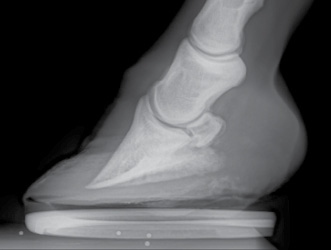

Radiographic observations. Examining the internal structures via a radiograph lends credence to the belief that the horse is club footed

(Figure 4).

“The palmar angle of the P3 is steep,” he says. “The horn-laminar zone (HLZ), measured at the top

portion of the dorsal wall and at the middle portion of the dorsal wall is equal, but there is an increase in the HLZ as you get to the distal portion of the dorsal wall.”

There also is some deformation of the coffin bone that causes concern.

“P3 is lipping at the distal margin of the dorsal portion of the bone, along with a curvilinear shape of the bone in general,” Silverman says. “The sole under this deformed section of P3 is only 10 mm thick. Mineralization of the collateral cartilages is quite advanced for a horse of this age

and experience.”